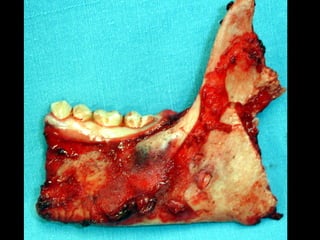

Eliminación de focos sépticos en bloque en paciente con osteitis

mandibular crónica

Pieza quirúrgica